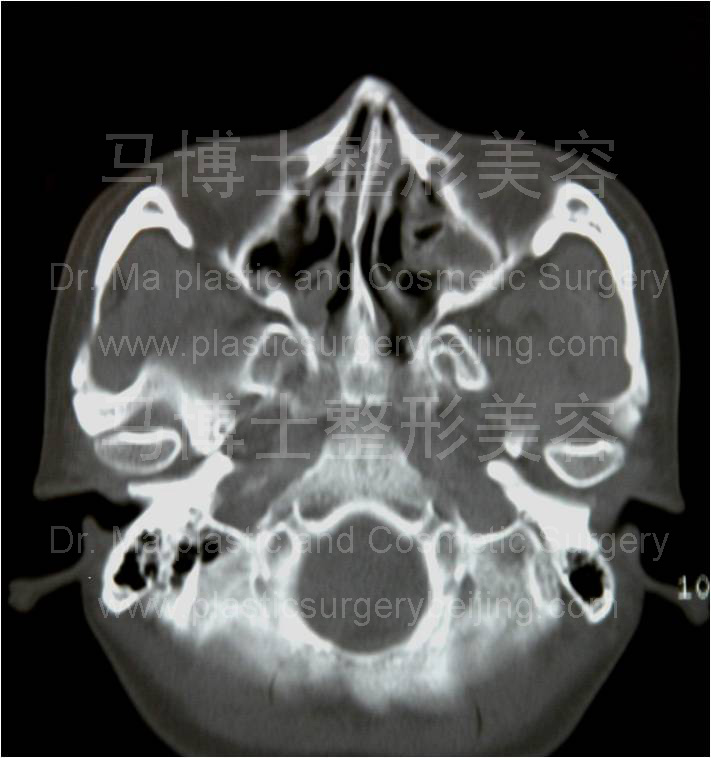

同一受术者术前术后CT断层,断面为经过颧弓的水平断面。左侧术前CT片可见颧弓弓度较大,右侧术后者弓度较小,颧弓变直。这种变化使两侧颧弓最突出点的距离变小。面部宽度变窄。